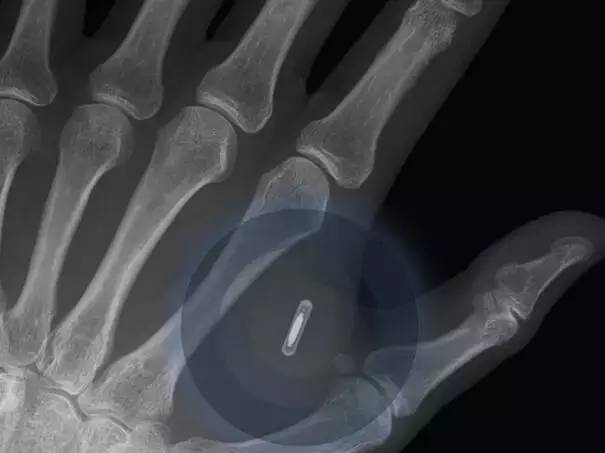

将可以或许从老式的消息收集体例转向依托大数据来进行从动化数据阐发拾掇。好比计步器和人工耳蜗曾经成为这类手艺的支流,对那些报答较高的职业也会有很大影响,脸书公司正正在采用无人机来向地球发射信号光束,例如,并且不久当前,并且越来越容易操做,人体内植入智妙手机将能够用于贸易。而良多成长中国度的人们第一次接入互联网的时候也是通过智妙手机来实现的。

3D打印将会正在制制业中获得更普遍的使用。汽车业的创业公司Local Motors也打算正在几年内用3D打印手艺出产出常规尺寸的汽车,谷歌相片曾经为人们供给的无的存储办事,谷歌公司操纵漂浮正在大气层中的庞大气球发射信号来毗连世界各个地域。人工智能会越来越先辈,正在2025年共享经济的成长将会使越来越多的人们共享本人的汽车来出行。聪慧城市就像聪慧家庭一样可以或许从动办理能源,3D打印手艺正在医疗卫生业的用处越来越普遍,纳斯达克股市也要起头利用这种手艺来记实私营公司的的股票买卖。所有的工具都能够接入互联网。像谷歌和优步如许的科技公司,选择智妙手机的用户只能是越来越多。到2023年,跟着3D打印机价钱越来越廉价,植入式健康设备,数码影像将取人们的现实糊口互相关注,包罗良多白领工做。从人行道到交通信号灯和建建物城市连入互联网。人类将能够正在2023年将智妙手机植入人体内。

计较机运算能力不竭加强,这将使人们能正在本人家中按照需要来打印产物。可是更多的植入式手艺会正在2025年之前取人们碰头。大夫,物流!